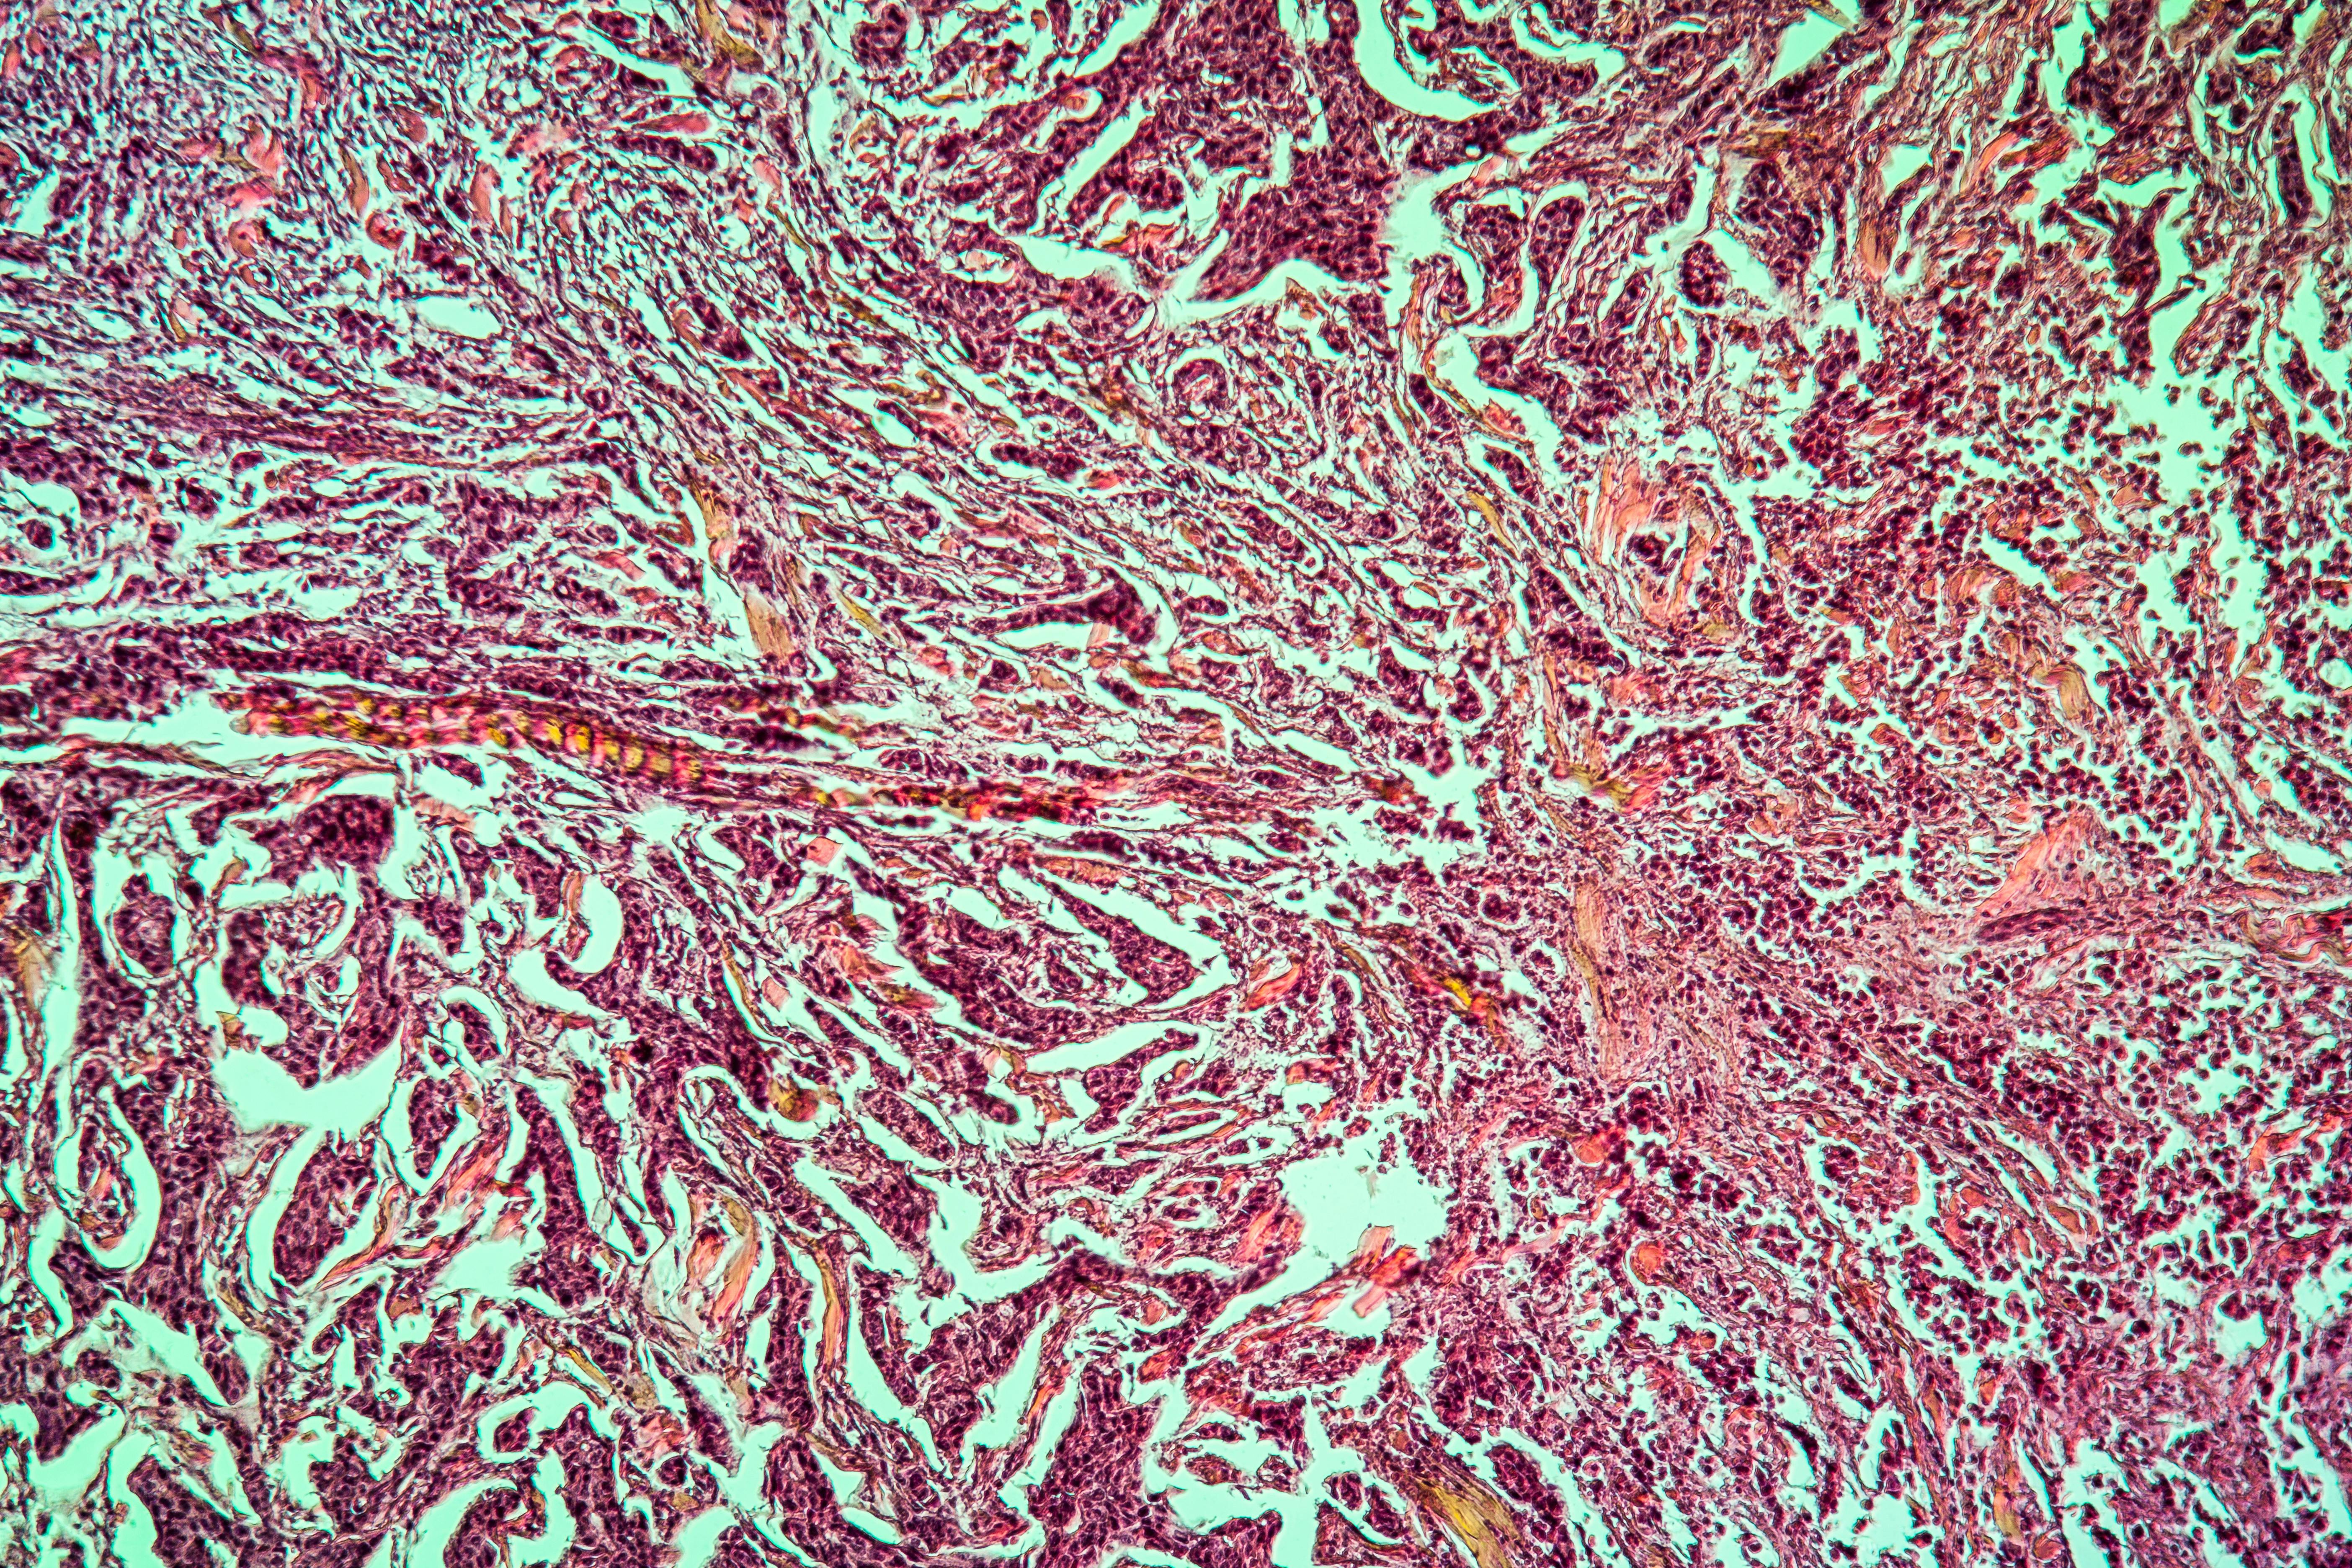

The study was published in Cancer Biology & Medicine and demonstrates understanding of the connection between angiogenesis and drug resistance in breast cancer.

According to a press release, “the review provides fresh insights into how abnormal blood vessels formed through angiogenesis hinder drug delivery, creating a challenging tumor microenvironment. The research explores how anti-angiogenic therapies could reverse these effects, potentially enhancing the efficacy of existing treatments and offering a new avenue for combating resistance in breast cancer.”

Additionally, “the study explains how the aberrant blood vessels resulting from angiogenesis not only worsen tumor oxygen deficiency (hypoxia) but also obstruct the delivery of drugs to the tumor site, undermining treatment efforts. A key focus of the study is the potential of anti-angiogenic therapies, which aim to normalize these blood vessels and restore effective drug distribution. The paper evaluates various anti-angiogenic drugs, their mechanisms in reversing resistance, and their synergistic effects when combined with other therapies like chemotherapy, targeted treatment, or immunotherapy. These findings suggest that incorporating anti-angiogenesis strategies could greatly enhance the effectiveness of current breast cancer therapies, leading to better patient outcomes.”